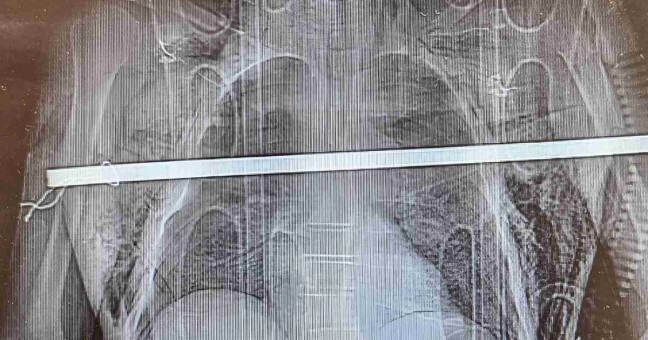

Mezitím se v olomoucké nemocnici se rozbíhá standardizovaný postup, přičemž podle Fritschera se lékaři shodli, že se s takovým raritním případem dosud nesetkali. „O příjezdu pacienta vědí na Oddělení urgentního příjmu a příslušný specialista, v tomto případě traumatolog,“ přiblížil mluvčí. Následně po zhlédnutí výsledků rentgenu a CT přichází na řadu aktivace lékařů z kardiochirurgické kliniky a hrudní chirurgie, kteří se podle Fritschera už cestou za vydatného deště domlouvali telefonicky na postupu. Mezitím leží Kučera stabilizovaný na ARO.

Zhruba v půl osmé večer se na operačním sále sešli lékaři se sestrami. kardiochirurgickému hrudnímu výkonu ještě předcházelo endoskopické vyšetření, které provedl Pavel Sychra z interní kliniky. „Jeho pomoc pro nás byla zásadní. Věděli jsme díky tomu, které orgány jsou poškozené a do jaké míry. Pan Kučera měl obrovské štěstí, protože tyč prošla hrudníkem, třetím mezižebřím, propíchla obě dvě plíce a v podstatě ležela na aortě. Dotkla se i jícnu, ale neperforovala ho. Minula těsně i plicní hily, tedy místa, kde vstupují cévy do plic. Stačilo několik milimetrů a už by mu nebylo pomoci,“ popsal stav pacienta kardiochirurg Martin Kaláb.